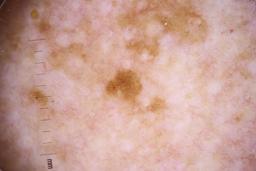

- Name: Challenge 2020: Training

- Number of images: 33,126

- Number of specified lesions: 32,701

- Number of specified patients: 2,056